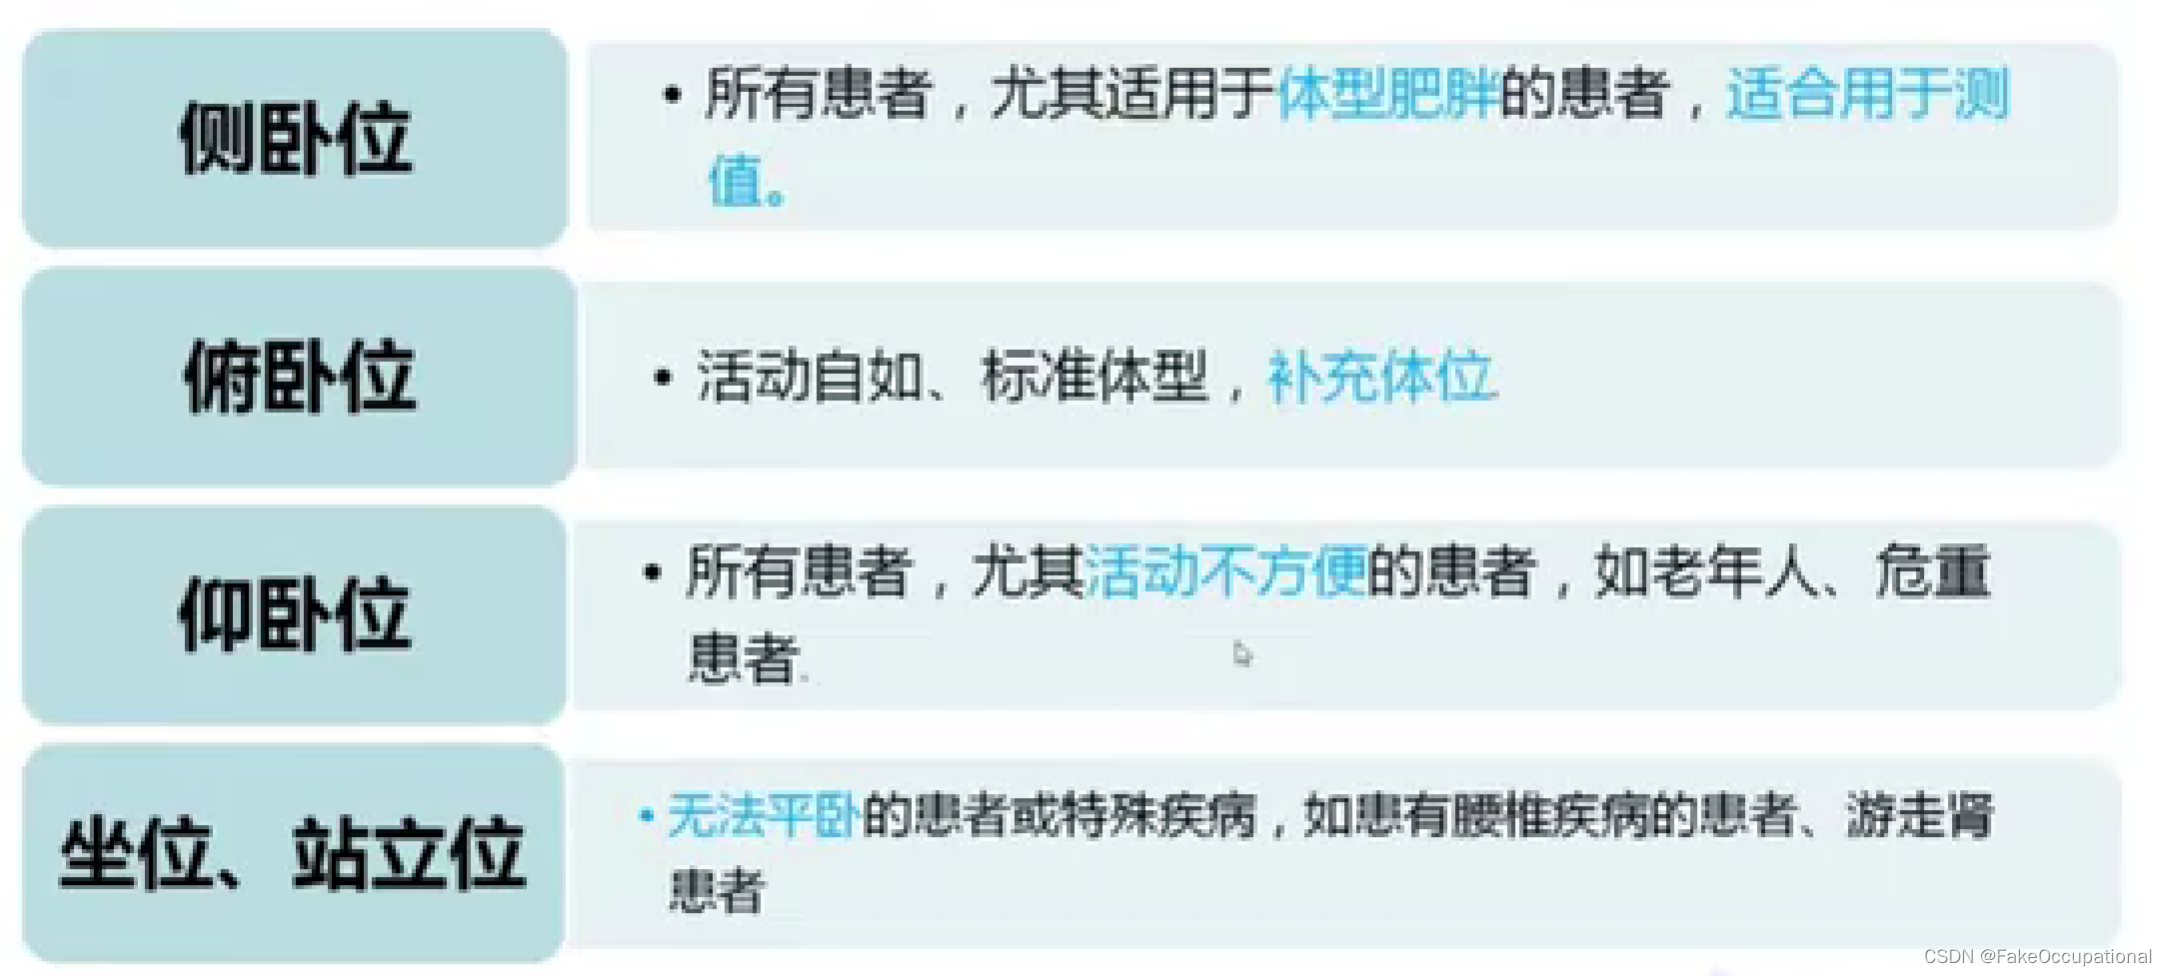

超声检查技术